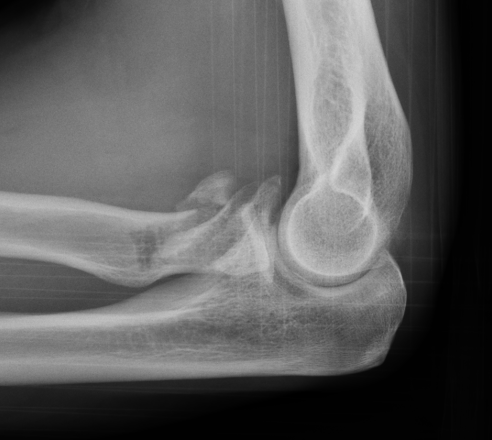

Completely displaced radial neck fracture

ORIF with plates